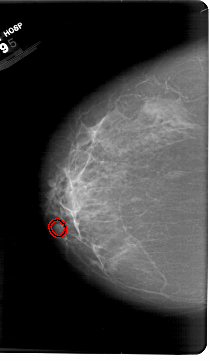

A_1386_1.LEFT_CC

LEFT_CC LINES 6841 PIXELS_PER_LINE 3976 BITS_PER_PIXEL 12 RESOLUTION 43.5 OVERLAY

FILE: A_1386_1.LEFT_CC.OVERLAY

TOTAL_ABNORMALITIES 1

ABNORMALITY 1

LESION_TYPE CALCIFICATION TYPE AMORPHOUS DISTRIBUTION LINEAR

ASSESSMENT 4

SUBTLETY 1

PATHOLOGY BENIGN

TOTAL_OUTLINES 1

BOUNDARY